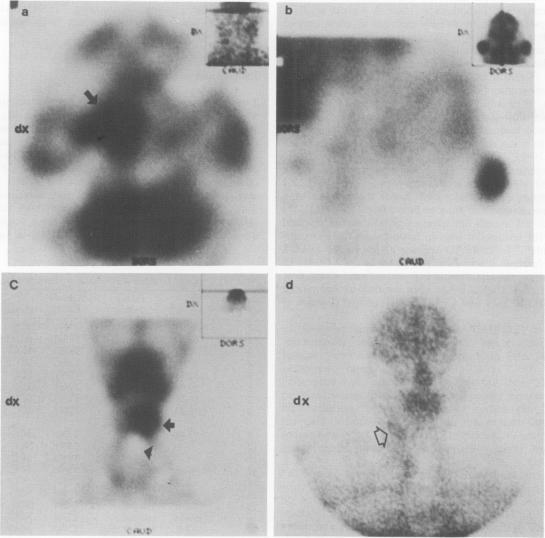

Twenty patients with malignant head and neck tumours were imaged with 99Tcm-labelled hexamethylpropylene amine oxime (HMPAO), a radiopharmaceutical generally used for blood flow studies. Before radiotherapy (RT), 93% of the tumours could be detected with single photon emission computed tomography (SPECT) and 45% with planar imaging. Whole tumour-to-background 99TcmHMPAO uptake ratios ranged from 3.6 to 1.0 (mean 1.7 +/- 0.6) in untreated tumours. There was a good correlation between tumour volume and uptake (r = 0.69, P = 0.002). Sixteen patients were reimaged during or shortly after radical RT. 99TcmHMPAO uptake was significantly lower after treatment (mean uptake ratio 1.2 +/- 0.3, P less than 0.001). However, RT associated changes in 99TcmHMPAO uptake were in agreement with the clinical response in only 63% of the studies. This study indicates that 99TcmHMPAO SPECT imaging can be used for pretherapeutic localisation of head and neck tumours. Although most tumours show a decrease in uptake after irradiation the poor association with tumour regression does not allow for reliable assessment of treatment response.

20例头颈部恶性肿瘤患者用99锝标记的六甲基丙烯胺肟(HMPAO)进行成像,HMPAO是一种常用于血流研究的放射性药物。放疗(RT)前,单光子发射计算机断层扫描(SPECT)可检测出93%的肿瘤,平面成像可检测出45%的肿瘤。未经治疗的肿瘤中,肿瘤与背景的99锝-HMPAO摄取率范围为3.6至1.0(平均1.7±0.6)。肿瘤体积与摄取之间存在良好的相关性(r = 0.69,P = 0.002)。16例患者在根治性放疗期间或放疗后不久再次成像。治疗后99锝-HMPAO摄取显著降低(平均摄取率1.2±0.3,P<0.001)。然而,在仅63%的研究中,99锝-HMPAO摄取的放疗相关变化与临床反应一致。本研究表明,99锝-HMPAO SPECT成像可用于头颈部肿瘤的治疗前定位。尽管大多数肿瘤在照射后摄取减少,但与肿瘤消退的相关性较差,无法可靠评估治疗反应。